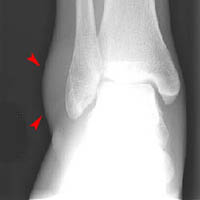

Now look at the radiographs below. Does this patient have a fracture?

Click on the image for the answer.

Mortise and lateral views of ankle